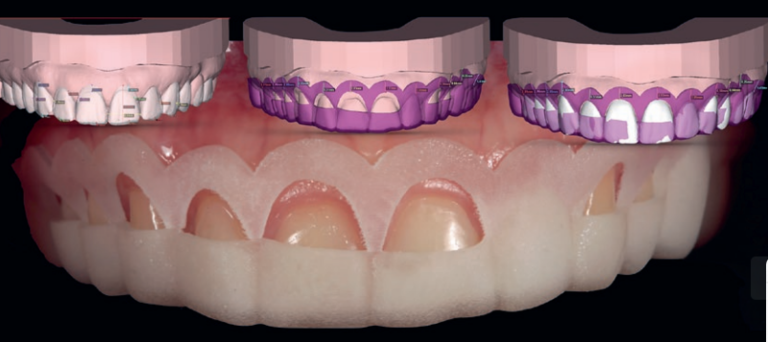

Dental Care with Dr. Rahman is a comprehensive clinic serving the Banani and Gulshan areas. We offer a full spectrum of treatments including routine family dentistry (fillings, root canals), advanced cosmetic procedures (Digital Smile Design, Veneers), and restorative solutions like 3-D guided implants and dentures.

Yes! We specialize in Invisalign Clear Aligners, which are the most popular choice for adults seeking a discreet way to straighten their teeth. This allows you to achieve a perfect smile without the look of traditional metal wire braces.

We certainly do. Our clinic is equipped with modern diagnostic technology, including Digital X-rays and CAD-CAM systems for digital restoration. We also utilize 3-D guided technology for precise implant placement.

Our clinic is equipped with modern dental technology including Digital Dental X-rays (safe, low-radiation imaging), CAD-CAM digital dental restoration (for precise, same-day crowns and restorations), 3D CT-guided dental implant planning, and the Invisalign clear aligner system. We also have strong laboratory partnerships to ensure the highest quality of prosthetic and cosmetic work.